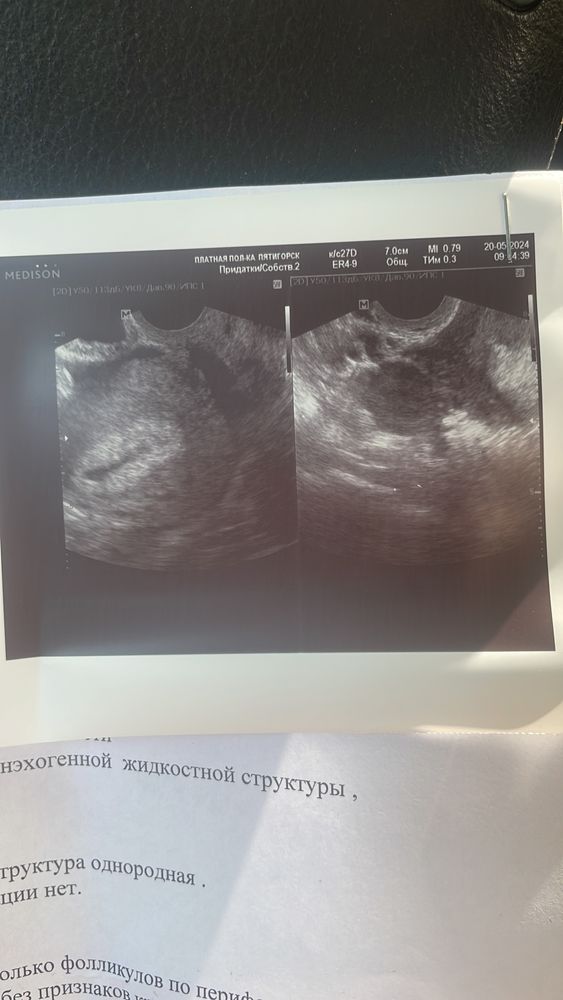

Была вчера на узи, пошла из-за того, что тесты положительные а у меня вылезла крапивница.

хгч 700 был по результатам лаборатории 3-4 недели беременности.

села почитать узи и ничего понять не могу, она сначала меня напугала, говорит кровь в матке, скорее выкидыш ждите. Кто умеет читать заключения, помогите 🙏🏻

Не эксперт, но когда только узнала о беременности лопатила весь интернет, то прочитала, что как минимум должно быть видно на узи желтое тело. О нем она у Вас ничего не пишет. Пишет только про фолликул 10 мм, а этого очень мало для зачатия (сама просто долго пыталась забеременеть и с этими фолликулами возилась)

Если есть возможность, то я бы переделала узи, желательно при хгч выше 1000

ХГЧ маленький, не увидит ничего, а если врач не очень, то и размеры может измерить не верно…. Предположительно ЖТ это фоликул 10 мм, маленькое конечно, но можно опять таки предположить что не верно померила, но и у ЖТ кровоток конечно есть, а тут пишет что нет, вот тут вопросики….

Передавайте узи в другом месте после ХГЧ в 10 000 ед. и ХГЧ в динамике обязательно!

Лучше попозже переделать, как 1000 будет. Жт нет; это странно. Возможно врач такое себе